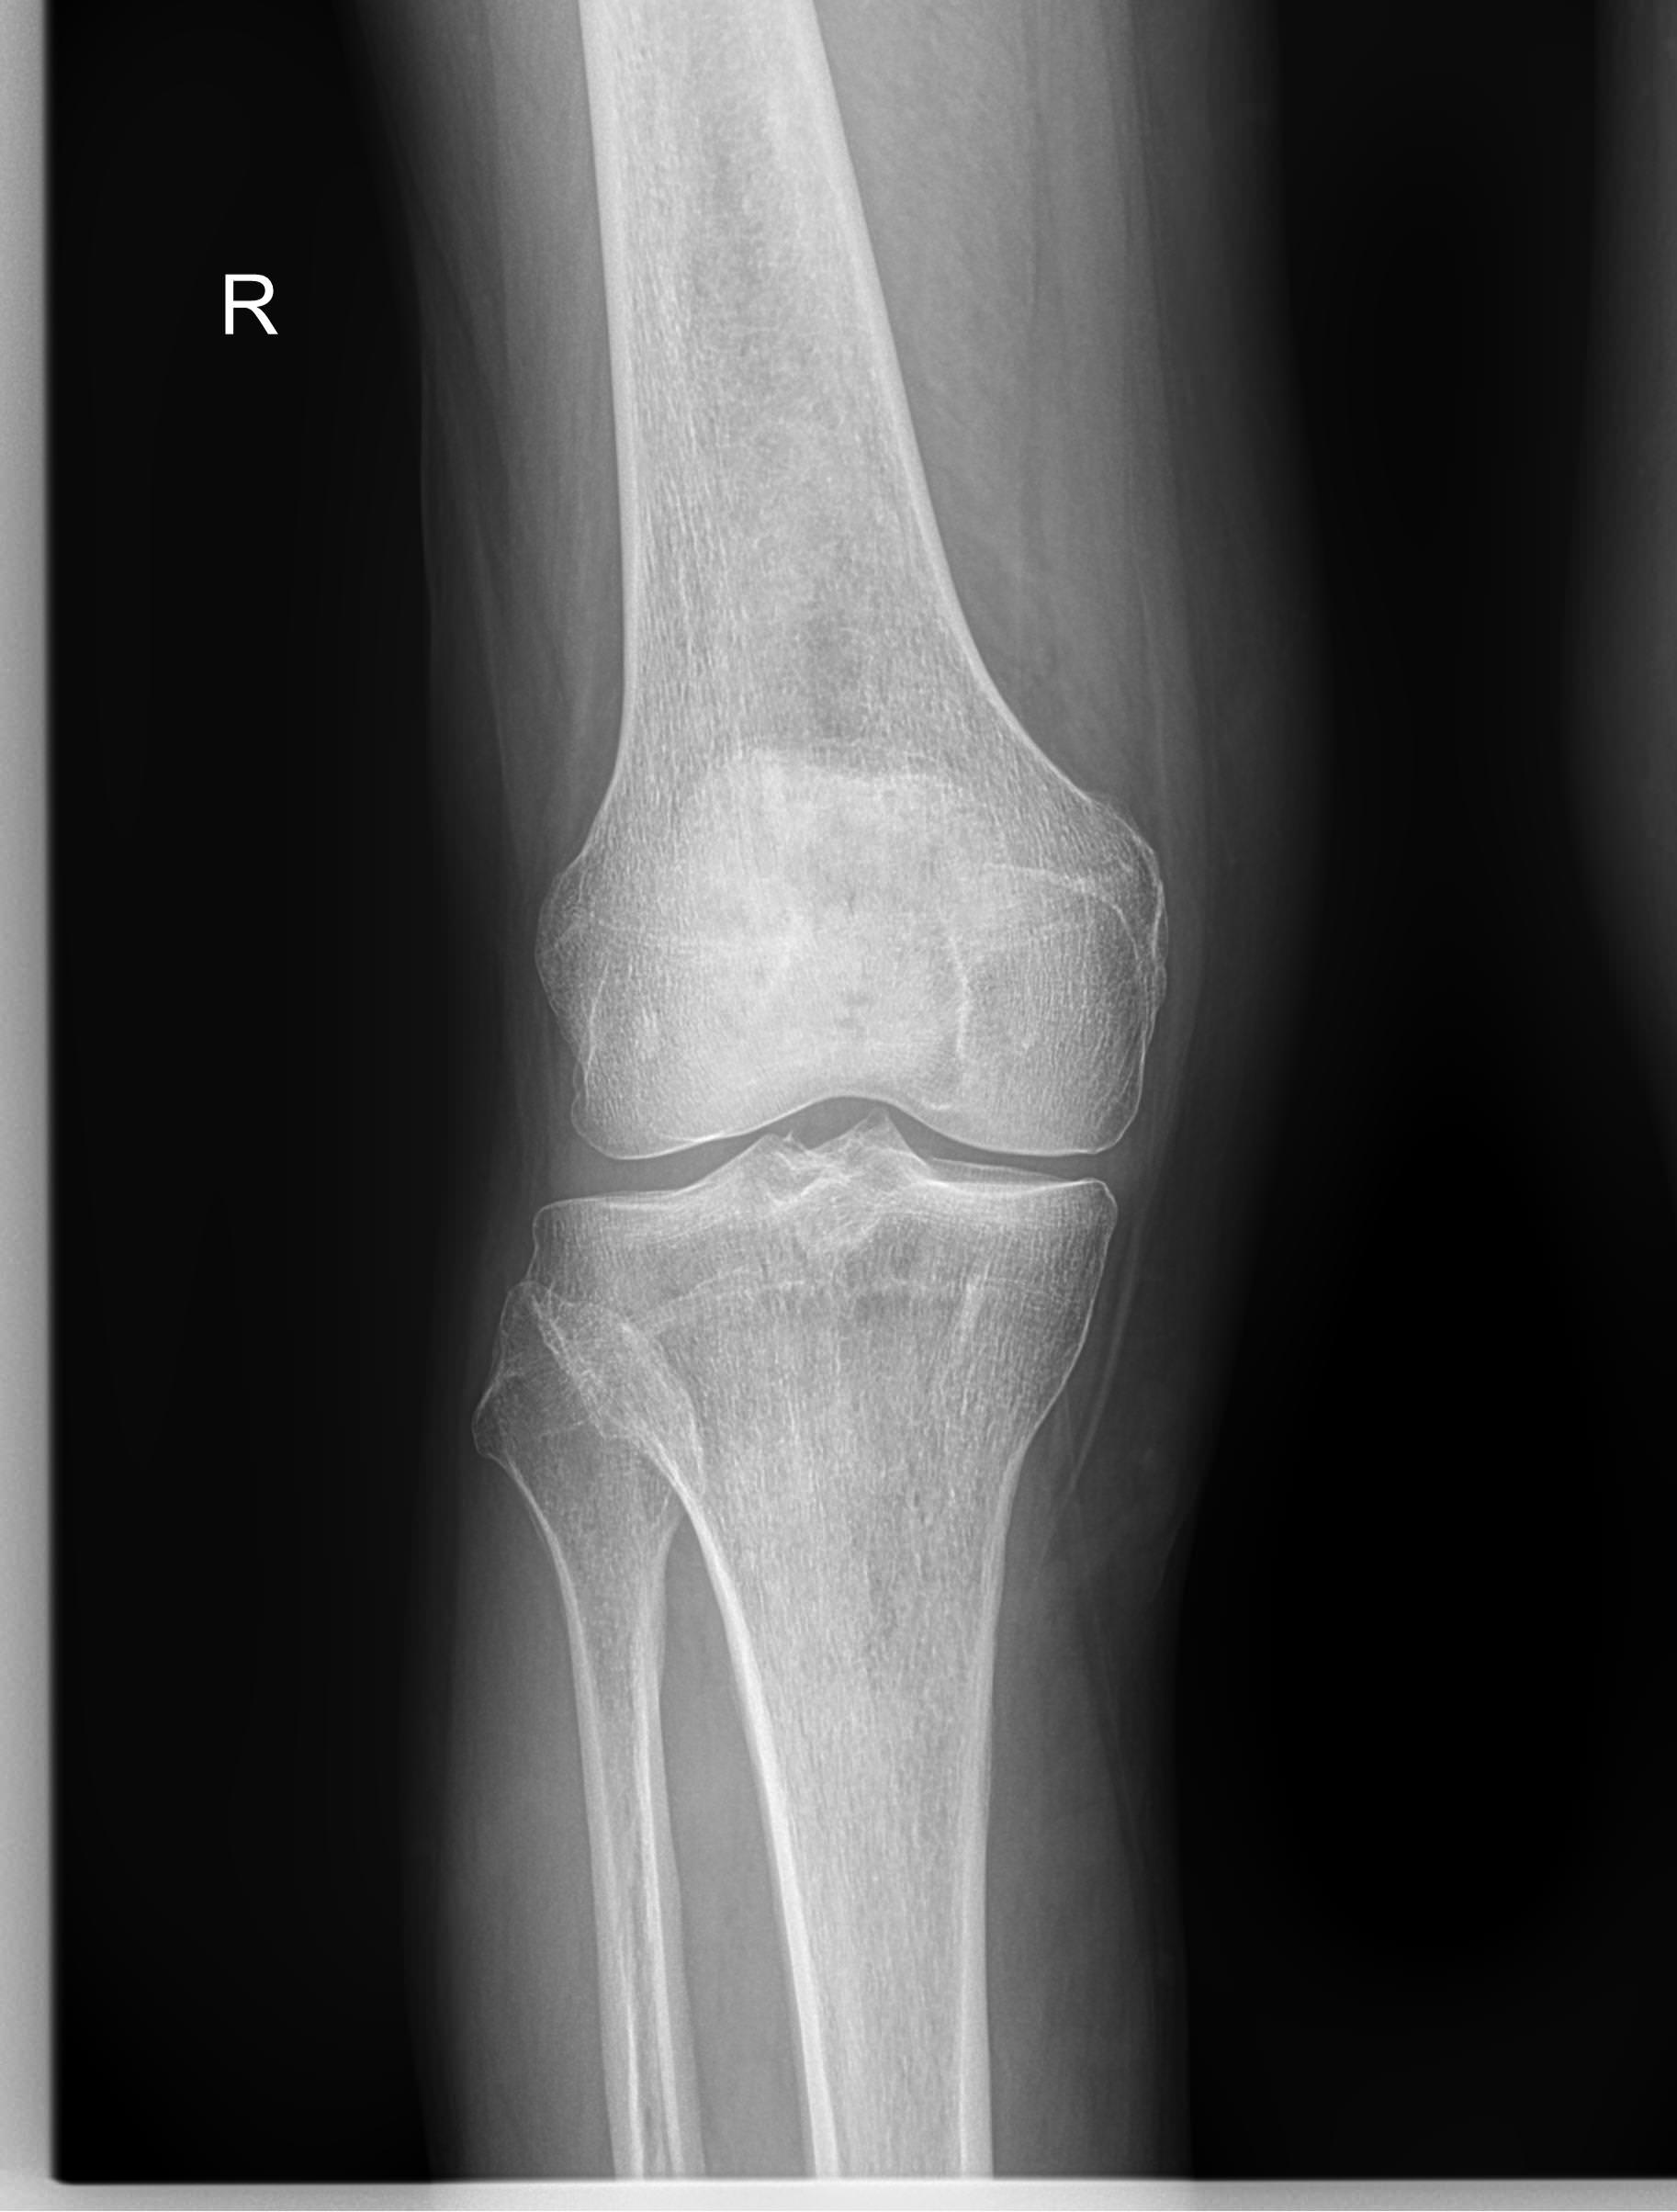

Рентген ― самый простой и быстрый метод диагностики поражения коленных суставов. Это неинвазивный и безболезненный , а также высокоинформативный способ увидеть внутреннее состояние колена. Современное рентгеновское оборудование использует минимально возможную дозу облучения. При этом на рентгенограмме отчетливо просматриваются части бедренной, малоберцовой и большеберцовой костей, надколенник, а также мягкие ткани вокруг них.

На рентгенограмме будут видны элементы сустава и патологические изменения в них:

• Суставная щель ― может быть расширена или сужена, причем неравномерно, иметь выпот, выросты, костные и хрящевые обломки;

• Соответствие друг другу суставных поверхностей ― естественное или вывих;

• Положение надколенника ― может быть неестественным;

• Состояние костной ткани: перелом, разрежение, уплотнение, размягчение, склерозирование;

• Мягкие ткани ― нормальные или отекшие, с инородными телами.